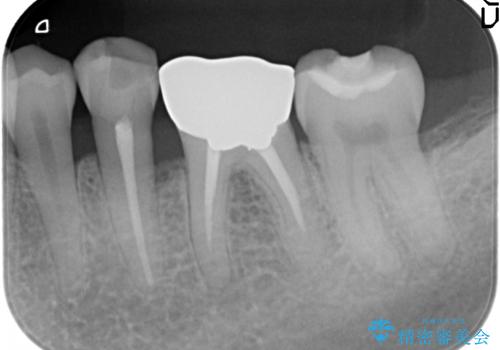

銀歯の下には再発した虫歯やセメントの漏出が見られ、丁寧に除去したのちセラミックによるクラウン・ブリッジ補綴を行います。

適合や精度の悪い銀歯は、時間の経過とともに虫歯の再発リスクが高まります。